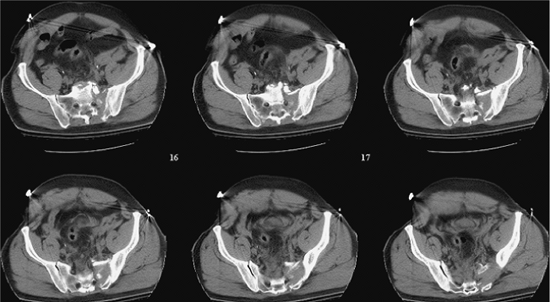

given to an analysis of the plain films and CT scans. On occasion,

iliac and obturator oblique radiographs of the pelvis are obtained in

patients with concomitant acetabular fractures. A two-dimensional CT

scan further delineates the specific sites of injury and direction of

displacement (Fig. 39.4). Just as important as

detailing the injury and local anatomy, the two-dimensional CT scan

also is used preoperatively to determine the number of screws that can

be inserted, the upper-sacral anatomy, the planned starting point on

the lateral ilium, and the screw direction and length needed to achieve

stable and balanced fixation (Fig. 39.5). Some

Figure 39.4.

These sequential CT axial images of the pelvis reveal much information. They demonstrate patient body habitus, fracture location, fracture comminution, displacement patterns, nerve root involvement, occult injuries not previously noted on plain films, local bone quality (including that of the upper-sacral dysplasia), soft-tissue degloving injuries, hematoma, contrast extravasation, soft-tissue and/or intra-abdominal air, among other important clinical details that may impact urgent and definitive care. The anticipated reduction maneuvers, clamp application sites, and the upper-sacral safe zone for iliosacral screw(s) can be assessed on such CT images of the pelvis. |